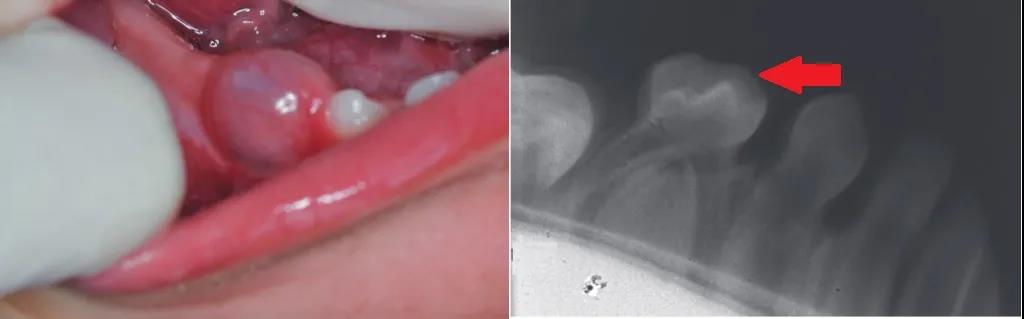

萌出囊肿是牙齿萌出前的牙槽处,出现的圆顶状的软组织病变[2],属于良性囊肿。表现是柔软的、半透明的,是液体(比如血清)在萌出牙的滤泡空间内蓄积所致,如下图所示。

但是也有一些病例提示,孩子会出现发痒、疼痛等感觉,尤其是咀嚼时,如果囊肿增大到2X2cm,如下图所示,会出现影响孩子进食,会让孩子感到烦躁,对于大孩子,可能出现心理问题。

如果想做个什么检查,这时做个牙片,能看到囊肿下面有牙齿在向上萌出,也能提示是这个问题。